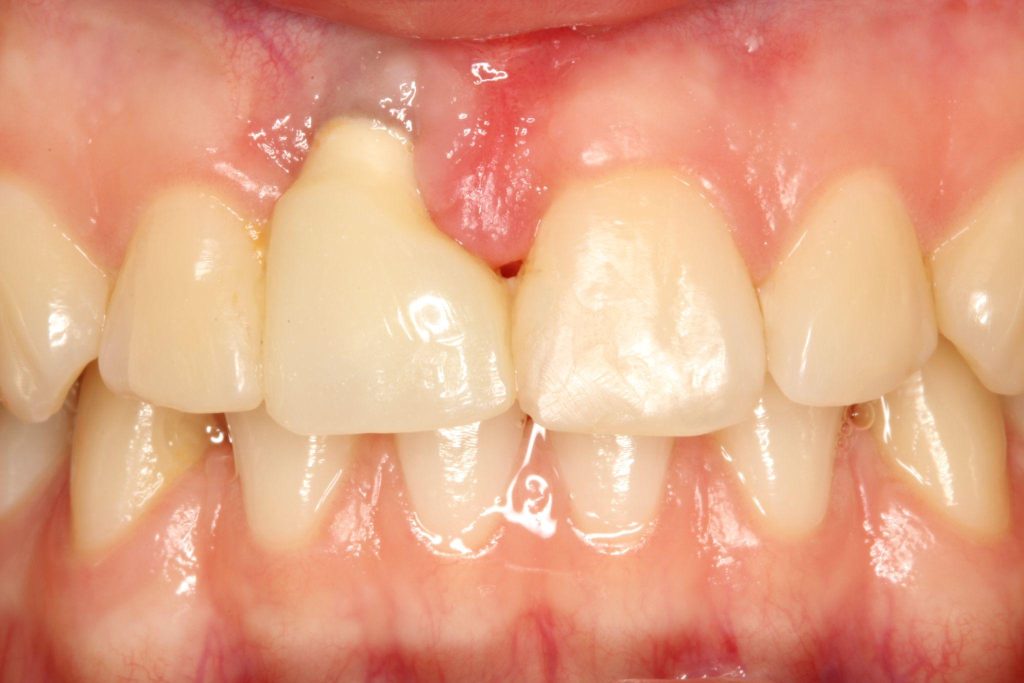

Aby osiągnąć taki efekt, musieliśmy przeprowadzić ekstrakcję złamanej górnej jedynki i w jej miejsce jednoczasowo wszczepić implant, a następnie na pozostałe zęby wykonać licówki i korony pełnoceramiczne w najjaśniejszym odcieniu.

Całość została zaprojektowana w harmonii z twarzą i rodzajem uśmiechu naszej Pacjentki. Leczenie trwało 3 miesiące.

Wykonał je lek.stom. Michał Badowski we współpracy z laboratorium Dentalscan (tech.dent. Joanna Gancarz).